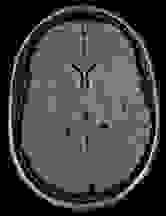

In Figure 1 we show a toy example of misjudgments that occur when evaluating the quality of a 2D MRI scan compared to degraded versions of the same image with the selected measures. PSNR even yields the same value for all the very different degradations, and all of the tested measures fail in the judgement of massive local information loss (d), as well as in the judgment of stochastic noise (e) versus block artefacts (f). This toy example served as an inspiration to study the behavior of the standard measures in real-life medical imaging tasks.

Figure 1: Illustrative toy example of problems occuring when using the standard FR-IQA measures PSNR/SSIM/LPIPS for the evaluation of medical images. Degradations have been added artificially to the reference (a) MRI scan: contrast enhancement (b), brightness change (c), hole (d), Gaussian White noise (e), jpeg compression (f). PSNR yields the same value for all degradations, SSIM and LPIPS fail to identify the hole (d), and misjudge the quality of (e) and (f).